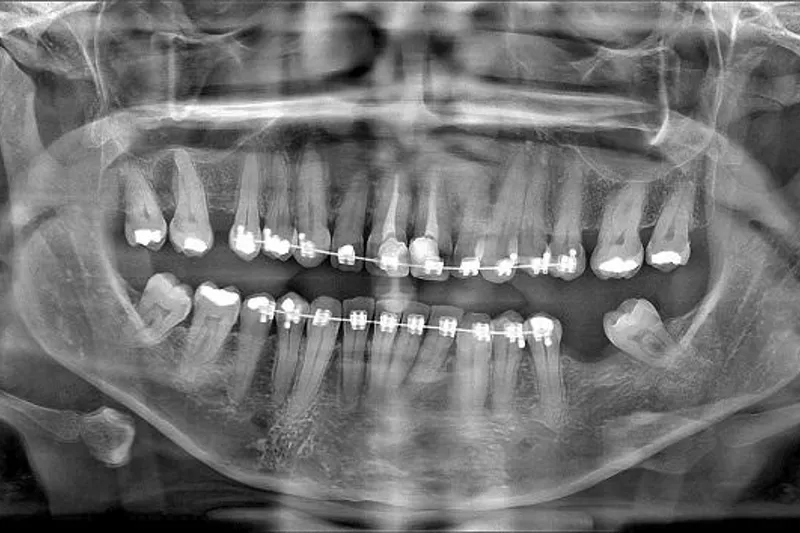

Panoramaoptagelse bør overvejes ved mistanke om kæbefraktur. Frakturer i underkæben diagnosticeres relativt sikkert på panoramaoptagelser. CBCT kan overvejes ved mistanke om kæbefraktur i overkæben og/eller mellemansigtet. CBCT kan også afsløre eventuelle tandfrakturer med relativt stor sikkerhed, forudsat at der ikke i strålefeltet er artefaktdannende genstande som fx metalkroner, stifter, rodfyldninger eller ortodontisk apparatur.

Rodfrakturer kan være svære at se på almindelige periapikale røntgenbilleder. De er kun synlige, hvis røntgenstrålerne løber nogenlunde parallelt med frakturlinjen, derfor er projektionen essentiel.

Hvis der er en stærk mistanke, men dette ikke verificeres med en intraoral røntgenoptagelse, kan du supplere med en CBCT-undersøgelse af området (vælg et lille field-of-view (FOV) og høj opløsning).

Igen skal du være opmærksom på, at rodfrakturer er vanskelige at diagnosticere på CBCT, hvis der er artefakter.